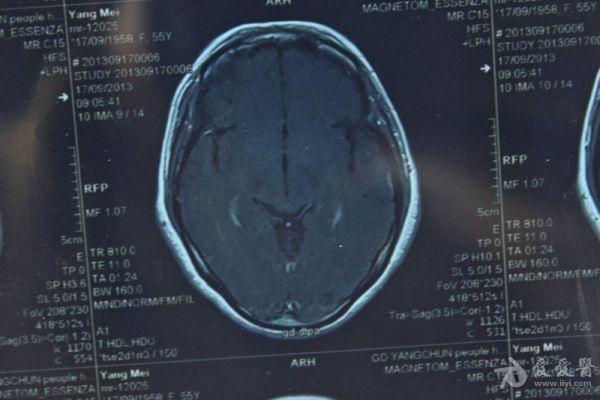

脑部占位病变CT,MRI图片,请帮忙诊断

最近感图样,无其它脑病病史

考虑脑膜瘤!!

磁共振没有平扫,增强矢状位没找到病灶。像脑膜瘤。

图片不是很清楚,应该是脑膜瘤!